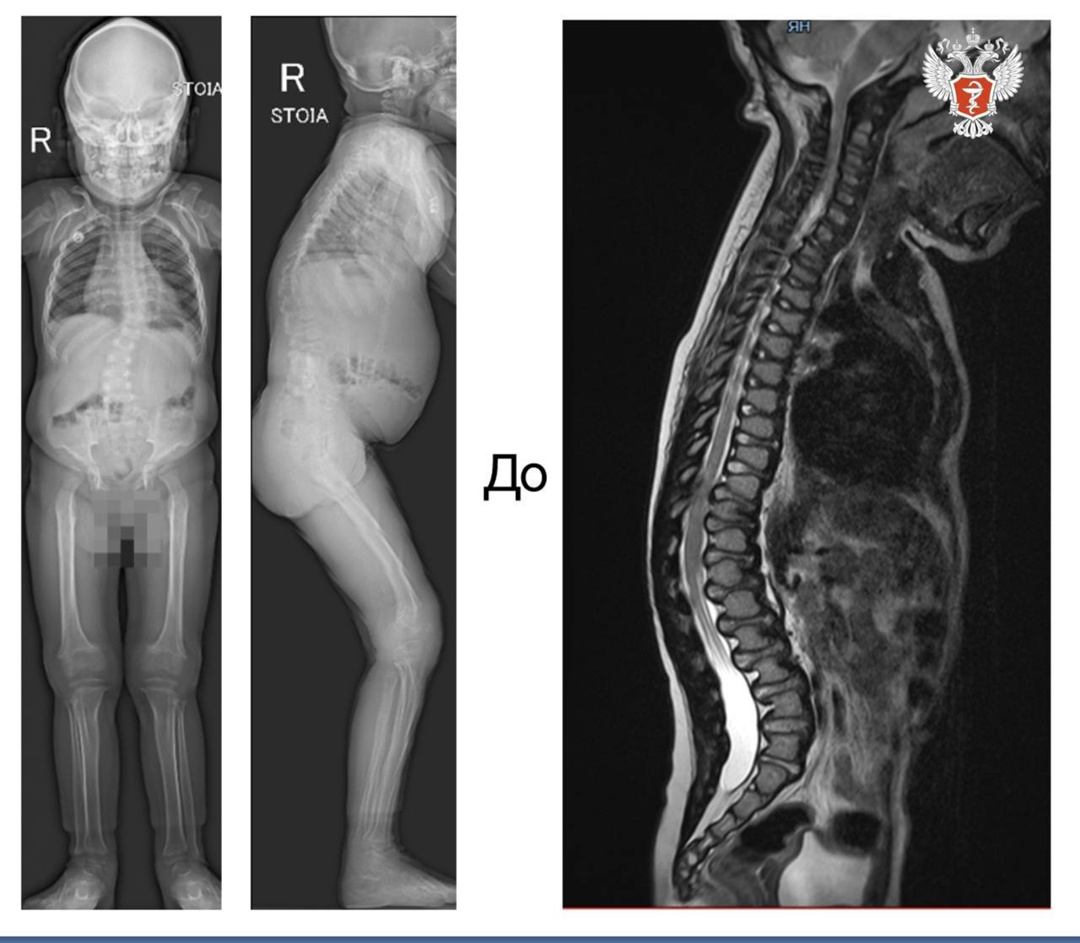

Семилетняя девочка поступила в НМИЦ травматологии и ортопедии им. ак. Г.А. Илизарова Минздрава России с мукополисахаридозом I типа.

С 11 месяцев родители пациентки стали замечать у дочки искривление позвоночника. Со временем деформация на уровне грудопоясничного перехода прогрессировала, усугублялись контрактуры верхних и нижних конечностей. Ребенок стал ходить на переднем отделе свода стопы.

➡️ В 2020 году была проведена операция, в ходе которой врачи выполнили декомпрессию спинного мозга на уровне краниовертебрального перехода.

— В 2024 году мы исправили кифотическую деформацию, освободили спинной мозг и стабилизировали позвоночник. После этого у ребенка значительно улучшилась двигательная активность, — рассказала лечащий врач отделения №9 Клиники патологии позвоночника и редких заболеваний НМИЦ травматологии и ортопедии им. ак. Г.А. Илизарова Минздрава России Полина Очирова.